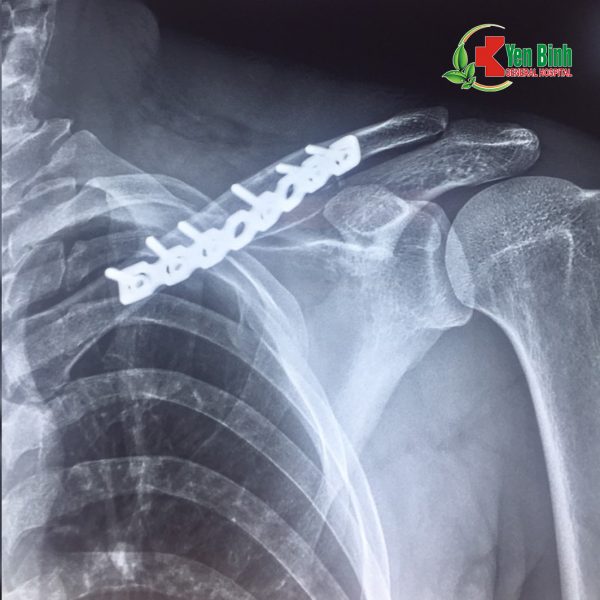

Hình ảnh chụp Xquang xương đòn trái gãy và sau khi đã phẫu thuật cố định xương cho bệnh nhân Hoàng Văn.H

(Hình ảnh do bác sỹ Bệnh viện Đa khoa Yên Bình cung cấp)